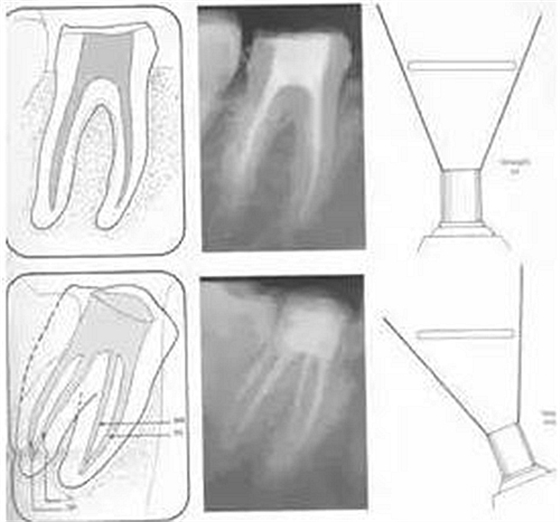

二、根管預(yù)備后形態(tài)

牙體缺損的修復(fù)需要將剩余牙體組織制備成一定形態(tài),以利修復(fù)體的良好固位。根管充填為了致密封閉根管系統(tǒng)也需要良好的根管預(yù)備后形態(tài)。

常規(guī)概念的根管預(yù)備后形態(tài)有: ( 1 )便宜形態(tài)( convenience form )。 ( 2 )保持形態(tài)( retention form )。

常規(guī)概念的根管預(yù)備后形態(tài)有:

( 1 )便宜形態(tài)( convenience form )。

( 2 )保持形態(tài)( retention form )

( 3 )抵抗形態(tài)( resistance form )。

1. 便宜形態(tài)

便宜形態(tài)是自切端或咬頜面朝向根尖的直線(xiàn)開(kāi)擴(kuò)尖錐形態(tài),減少污染物推出根尖孔,方便沖洗、根管充填和側(cè)壁施壓。

2. 保持形態(tài)

保持形態(tài)是根尖狹窄部?jī)?nèi) 1 — 2mm 的一段距離,由擴(kuò)大器回轉(zhuǎn)切割而不貼根管壁提拉切割制成,是擴(kuò)大器的原始形態(tài)(近似平行)。在測(cè)試主牙膠尖時(shí)給測(cè)試者有一個(gè)牽引抵抗 (tugback) 的感覺(jué)。

3. 抵抗形態(tài)

抵抗形態(tài)是根管預(yù)備的根尖形態(tài),它是由擴(kuò)大器或根管銼尖端 75 度角自然切割而成。其目的是防止根管充填材超出根尖孔,并且使根尖封閉更加嚴(yán)密。

( 1 )直線(xiàn)通路:根管治療時(shí)需要一個(gè)直線(xiàn)通路,直線(xiàn)通路能夠達(dá)到根尖三分之一

測(cè)量標(biāo)準(zhǔn):以允許根管器械直線(xiàn)并直接進(jìn)入根尖 1/3 且不接觸冠方各壁為標(biāo)準(zhǔn)。

( 2 )髓腔其他改變:如髓室頂、繼發(fā)性牙本質(zhì)、修復(fù)性或增齡性牙本質(zhì)。見(jiàn)左圖。

右圖中有繼發(fā)性牙本質(zhì),切削后獲得直線(xiàn)通路。